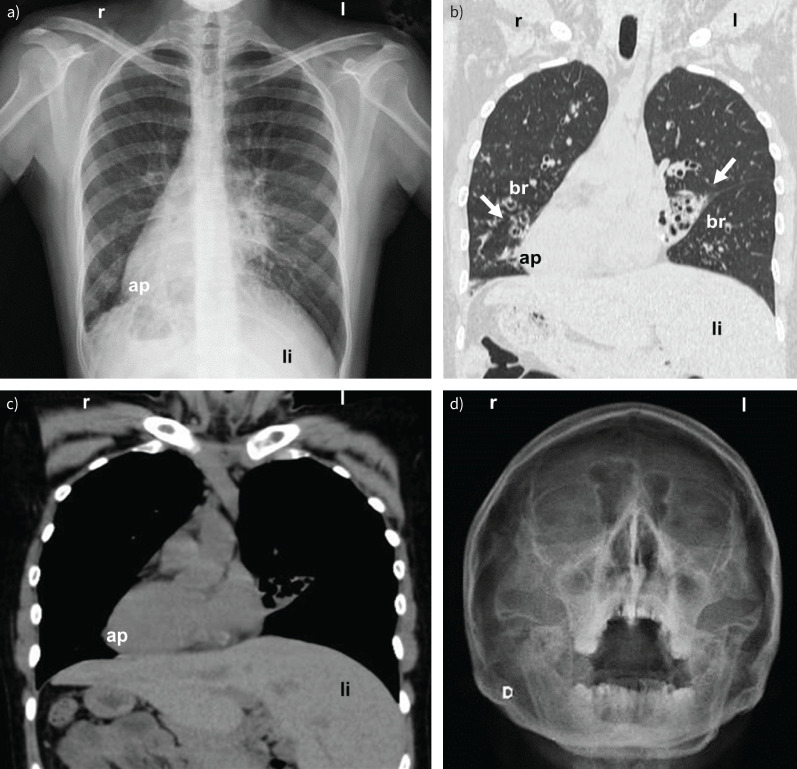

一个有趣的案例,一个28岁的女性慢性呼吸道症状和倒立部位。电镜超微结构分析是发现罕见综合征的一个亮点。复杂诊断的一堂课!@cime_conicet, @virkinal https://bit.ly/4jHzdW5。

An intriguing case of a 28-year-old woman with chronic respiratory symptoms and situs inversus. Ultrastructural analysis by electron microscopy is a highlight in the discovery of a rare syndrome. A lesson in complex diagnostics! @cime_conicet, @virkinal https://bit.ly/4jHzdW5.